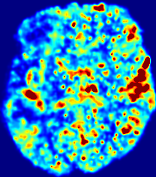

LesionRefer to captionRefer to captionRefer to captionRefer to captionRefer to captionRefer to caption𝐕rgbsubscript𝐕𝑟𝑔𝑏{\bf{V}}_{rgb}Refer to captionRefer to captionRefer to captionRefer to captionRefer to captionRefer to caption𝐕2subscriptnorm𝐕2{\|\bf{V}}\|_{2}Refer to captionRefer to captionRefer to captionRefer to captionRefer to captionRefer to captionRefer to caption3.53.53.52.82.82.82.12.12.11.41.41.40.70.70.70.00.00.0(mm/s)𝑚𝑚𝑠(mm/s)D𝐷DRefer to captionRefer to captionRefer to captionRefer to captionRefer to captionRefer to captionRefer to caption0.0200.0200.0200.0160.0160.0160.0120.0120.0120.0080.0080.0080.0040.0040.0040.0000.0000.000(mm2/s)𝑚superscript𝑚2𝑠(mm^{2}/s)Slice #1Slice #2Slice #3Slice #4Slice #5Slice #6

Figure 4: PIANO feature maps for another patient in the ISLES 2017 training set, where the lesion is located in the right hemisphere. Top row: segmented stroke lesion region (white) on different slices. The corresponding slices for the PIANO feature maps are shown in the following rows.

For a better insight into an estimated velocity field 𝐕𝐕{\bf{V}} and diffusion field 𝐃𝐃{\bf{D}}, we compute the following maps: (1) 𝐕rgbsubscript𝐕𝑟𝑔𝑏{\bf{V}}_{rgb}: Color-coded orientation map of 𝐕=(Vx,Vy,Vz)T𝐕superscriptsuperscript𝑉𝑥superscript𝑉𝑦superscript𝑉𝑧𝑇{\bf{V}}=(V^{x},V^{y},V^{z})^{T}, obtained by normalizing 𝐕𝐕{\bf{V}} to unit length and mapping its 3 components to red, green, blue respectively; (2) 𝐕2subscriptnorm𝐕2\|{\bf{V}}\|_{2}: 222 norm of 𝐕𝐕{\bf{V}}; (3) D𝐷D: scalar field in Eq. 5.

Fig. 3 and Fig. 4 show the PIANO feature maps estimated from two ISLES 2017 patients: all are highly consistent with the lesion in both cases. Details of the blood flow trajectories are revealed in 𝐕rgbsubscript𝐕𝑟𝑔𝑏{\bf{V}}_{rgb} by the ridged patterns and the sharp changes of colors in the unaffected (right) hemisphere, while the flat patterns appearing within the lesion provide little directional information about the velocity and indicate low velocity magnitudes. Velocity magnitudes are more directly visualized via 𝐕2subscriptnorm𝐕2\|{\bf{V}}\|_{2}, from which one can easily locate the lesion where 𝐕2subscriptnorm𝐕2\|{\bf{V}}\|_{2} is low. D𝐷D also indicates lower diffusion values in the lesion, though with less contrast potentially due to the fact that it captures the accumulated effect of CA diffusion at the voxel-level.